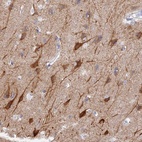

Immunohistochemical staining of human cerebral cortex shows strong cytoplasmic positivity in neuronal cells.